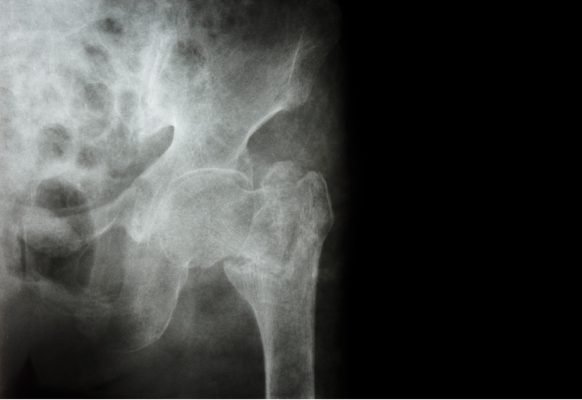

Hip Fractures

The rate of hip fractures in the elderly is rising yearly, and most causes are accidental falls. For example, in 95% of hip fracture cases in individuals over 65, the cause of the fracture is a fall.